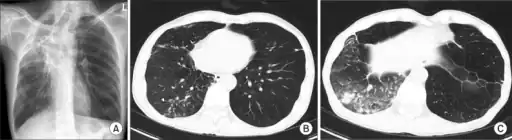

- Usually infects young children with cervical lymphadenitis or adults with chronic pulmonary disease, (mostly with previously documented pneumoconiosis).